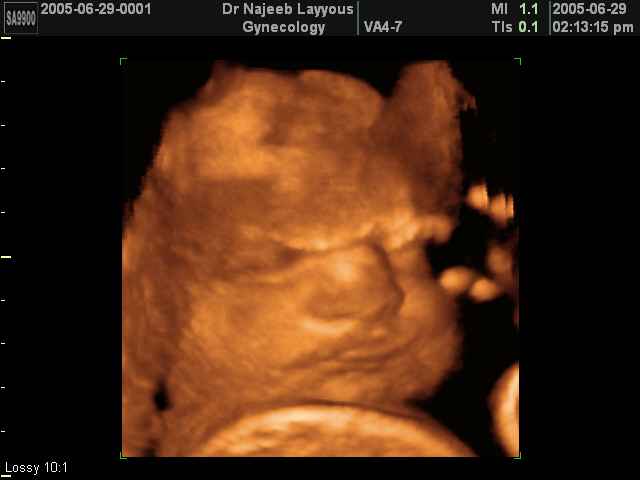

صور لتصرفات الجنين داخل الرحم بجهاز الالتراساوند ثلاثي الأبعاد | الدكتور نجيب ليوس

صور بجهاز الموجات فوق صوتية ثلاثي الأبعاد لتصرفات الجنين داخل الرحم